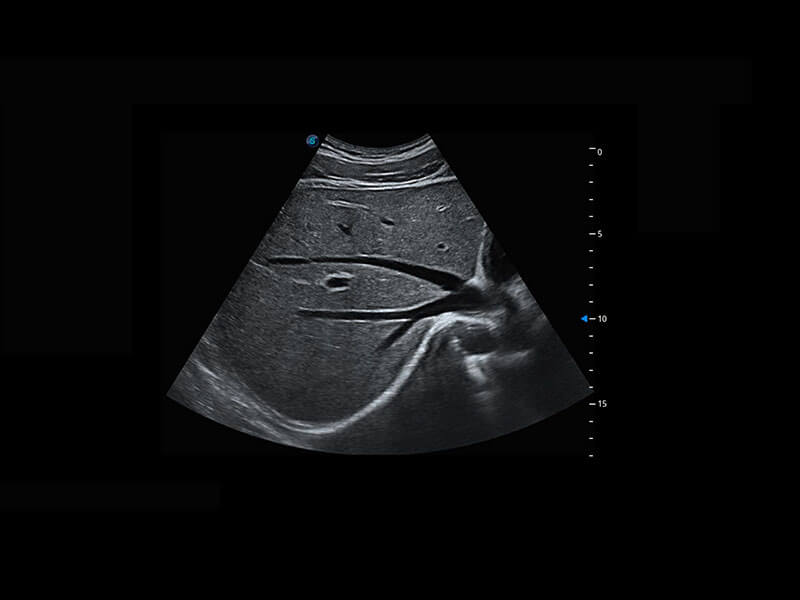

P60搭载一系列胎儿心脏成像技术,实现精细的胎儿心脏评估。

四腔切面